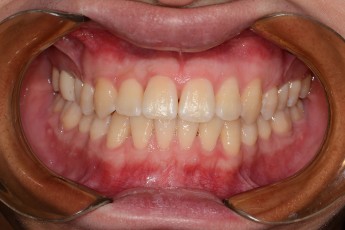

BEFORE & AFTER